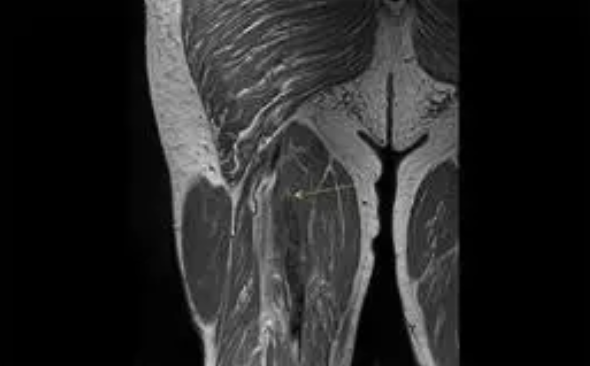

Al respecto, el doctor Mostien y sus compañeros del Hospital Jessa (en Hasselt-Bélgica) y la Universidad de Hasselt tomaron biopsias musculares de pacientes con Covid en estado crítico antes y después de la admisión a cuidados intensivos. Un total de 18 pacientes fueron analizados para el proyecto. Concretamente su vasto lateral, el músculo más grande y poderoso del muslo, biopsiado varias veces desde 1-3 días antes de la admisión en la UCI hasta 5-8 días después de la admisión. Los pacientes tenían una edad media de 69 años y el 82 por ciento eran hombres.

Las fibras musculares de Tipo I crecieron un 5,74 por ciento y las fibras de tipo II se contrajeron un 5,17 por ciento. Sin embargo, las fibras de cuatro pacientes aumentaron un 62 por ciento, en las de tipo I, y un 32 por ciento en las de tipo II.

«Estos pacientes fueron excluidos de los cálculos. Los pacientes restantes mostraron un desgaste muscular significativo, dice el doctor Mostien. Las fibras de tipo I se redujeron en un 11 por ciento y las fibras de tipo 2 en un 17 por ciento. No se sabe por qué las fibras musculares aumentaron de tamaño en cuatro de los pacientes, pero una posibilidad es que su respuesta inmune al Covid dañara sus mitocondrias, las diminutas estructuras que proporcionan energía a las células», han explicado los investigadores.